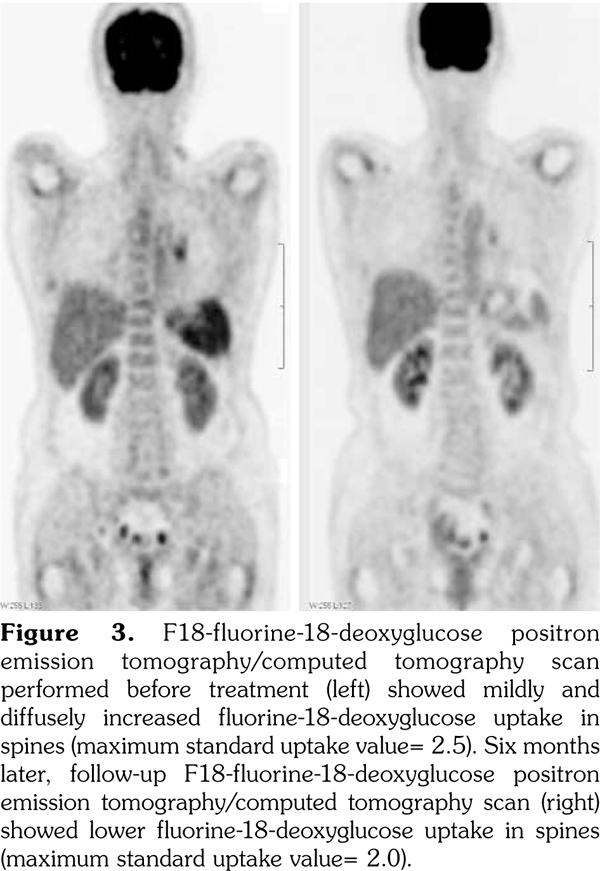

A 53-year-old female patient suffered from pain over most of her body, particularly the joints and the throat. In addition, skin rashes on the trunk without pruritus were noted. She had visited the Rheumatology, Neurology, and Orthopedic Outpatient Department several times. A chest computed tomography (CT) was performed which revealed multiple lymphadenopathies over cervical, mediastinal, and axillary areas. A positron emission tomography (PET)/CT revealed increased fluorine-18-deoxyglucose (FDG) uptake in many lymph nodes including the bilateral neck, axillae, mediastinum, bilateral pulmonary hili, abdominal paraaortic region, iliac regions, and inguinal regions as well as the bone marrow and the spleen (Figure 1). In addition, mild and diffuse increase of FDG uptake in the bone marrow was noted. Lymphoma was suspected first. After discussing with the patient, thoracoscopic mediastinal lymph node biopsy was performed. Fifteen lymph nodes were taken and the results showed histiocytic infiltration in sinusoid area and anthracotic pigment deposition. Reactive lymphoid follicle hyperplasia and focal fibrocalcified nodule formation were also noted. No tumor cell was seen. Gallium-67 (Ga-67) scan was conducted and no gallium-avid tumor was seen throughout the whole body (Figure 2). The laboratory data were negative for antinuclear antibodies, rheumatoid factor- immunoglobulin M, and extractable nuclear antibody, while alanine aminotransferase was high. The final diagnosis was AOSD. In our case, there were no symptoms or signs of either high fever or debilitating joint although the FDG PET showed multiple FDG-avid lesions in the whole body scan. According to the experience of our rheumatologists, methylprednisolone (Metisone) 4 mg/day and non-steroidal anti-inflammatory drugs were prescribed initially and the response to treatment was good. Six months later, the follow- up PET/CT showed complete remission of the FDG-avid lesions seen in the previous PET/CT (Figure 1) and the patient’s symptoms relieved. A written informed consent was obtained from the patient.

In this study, we present the FDG PET/CT and Ga-67 scan findings of a patient who met the Yamaguchi classification criteria for AOSD. The FDG PET/CT scan was not helpful in diagnosing AOSD in this case since lymphoma could not be ruled out. However, the FDG PET/CT scan results were useful for evaluating the distribution and severity of the disease. A negative Ga-67 scan could be beneficial as it would exclude lymphoma. After the diagnosis of AOSD was established, the patient received nonsteroidal anti-inflammatory drugs and glucocorticoids with a good response. Disease activity and therapeutic response were monitored by FDG PET/CT and the findings of a scan performed six months after treatment were negative.(13)